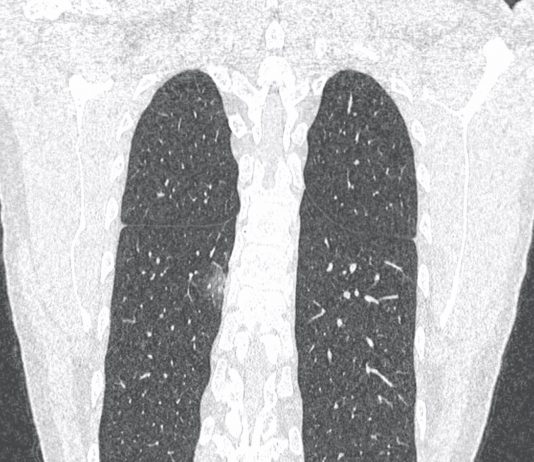

56-year-old male patient presented to the ED with fever,...